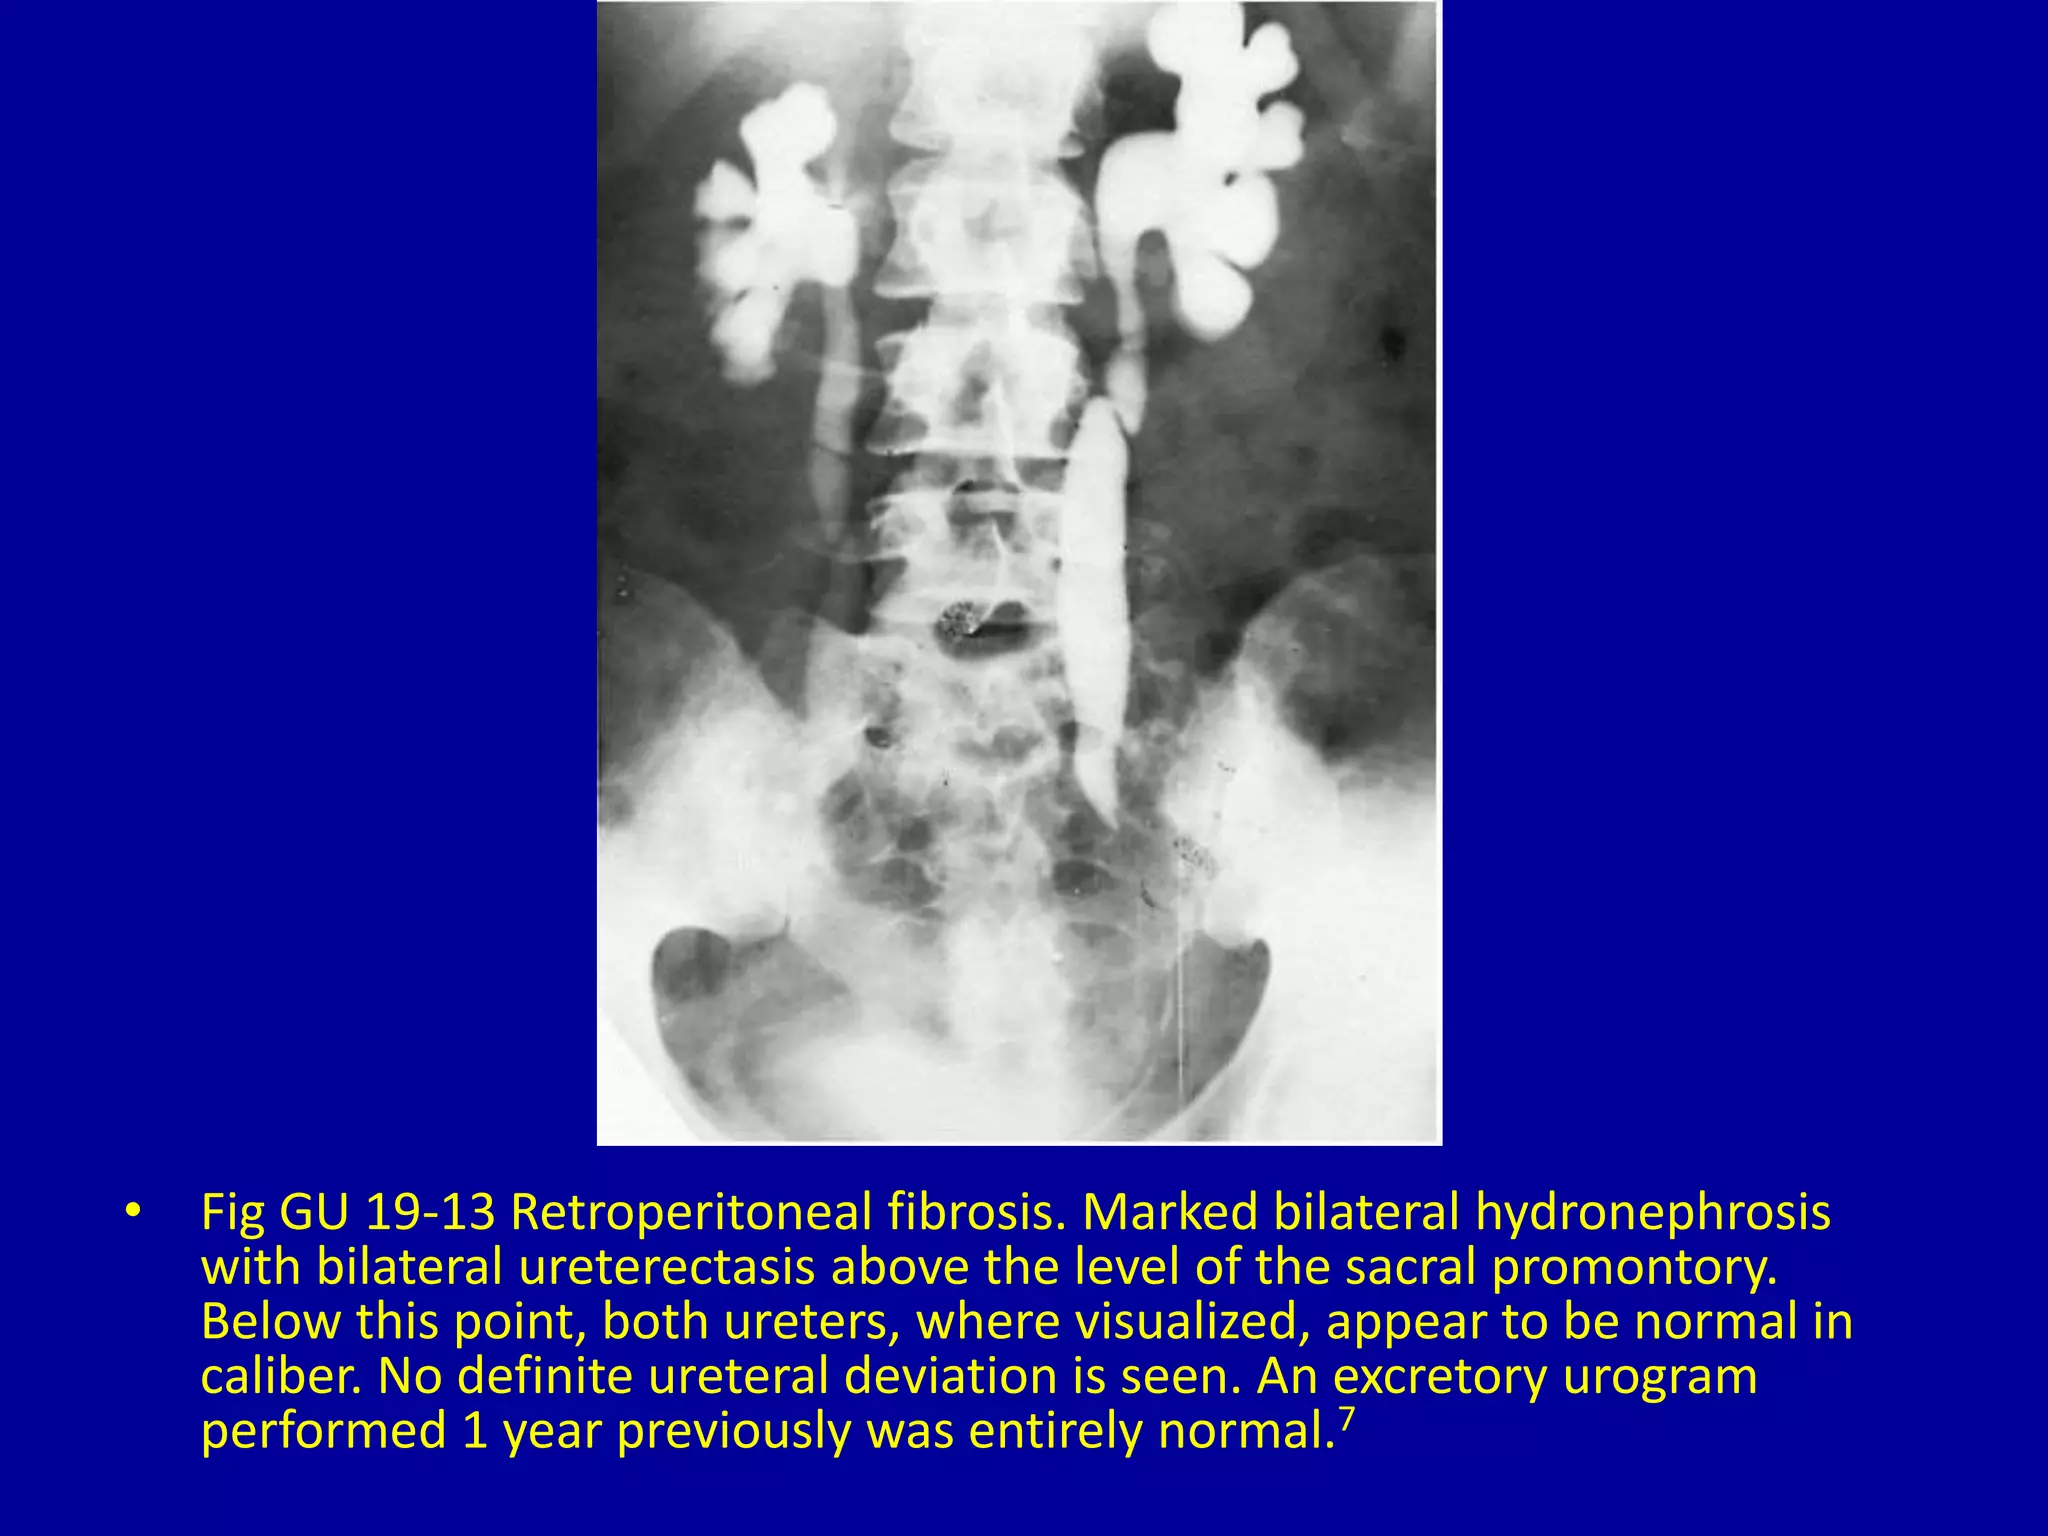

• Fig GU 19-13 Retroperitoneal fibrosis. Marked bilateral hydronephrosis

with bilateral ureterectasis above the level of the sacral promontory.

Below this point, both ureters, where visualized, appear to be normal in

caliber. No definite ureteral deviation is seen. An excretory urogram

performed 1 year previously was entirely normal.7

• Fig GU19-13 Retroperitoneal fibrosis. Marked bilateral hydronephrosis with bilateral ureterectasis above the level of the sacral promontory. Below this point, both ureters, where visualized, appear to be normal in caliber. No definite ureteral deviation is seen. An excretory urogram performed 1 year previously was entirely normal.7